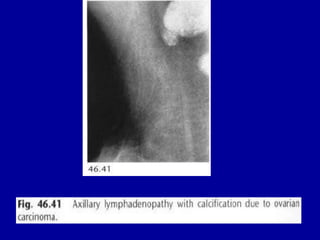

• Fig. 46.43 Keloid. A lobulated soft-tissue

opacity is demonstrated overlying the upper

part of the breast (arrows).